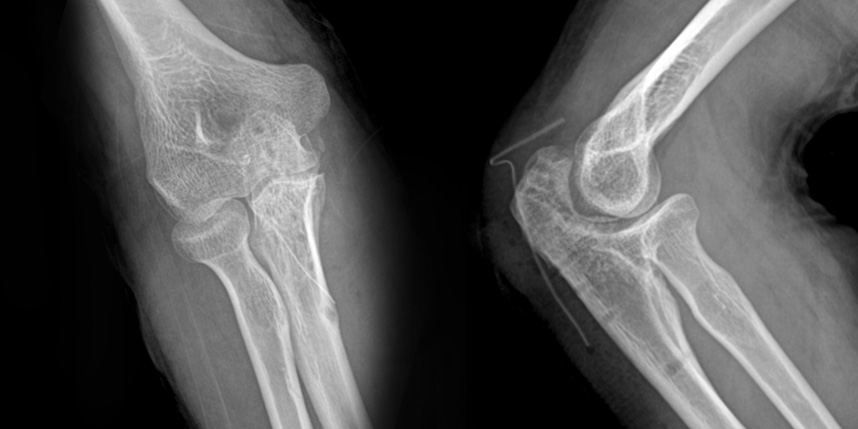

무릎 골절

상완골 골절